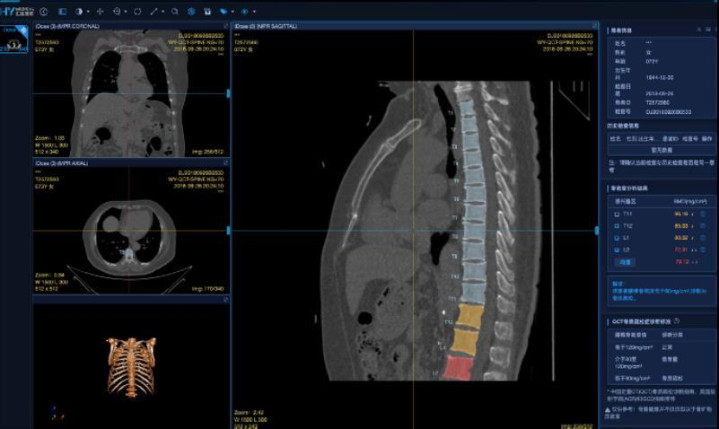

面对市场上多样的筛查技术,如何选择适合自身的体检方案呢?据悉,在骨密度检测领域,爱康集团提供的QCT骨密度人工智能检测,因其可在胸部CT扫描时同步完成骨密度测量,便捷高效且精准度更高,正成为越来越多人的新选择。同时,爱康联合合作伙伴推出的“骨力宝”人工智能膝关节、髋关节健康评估,借助人工智能与大数据分析,能够更早地揭示骨关节退行性变化的趋势,为公众提供了一体化的骨健康管理解决方案。

爱康AI定量CT骨密度检测系统